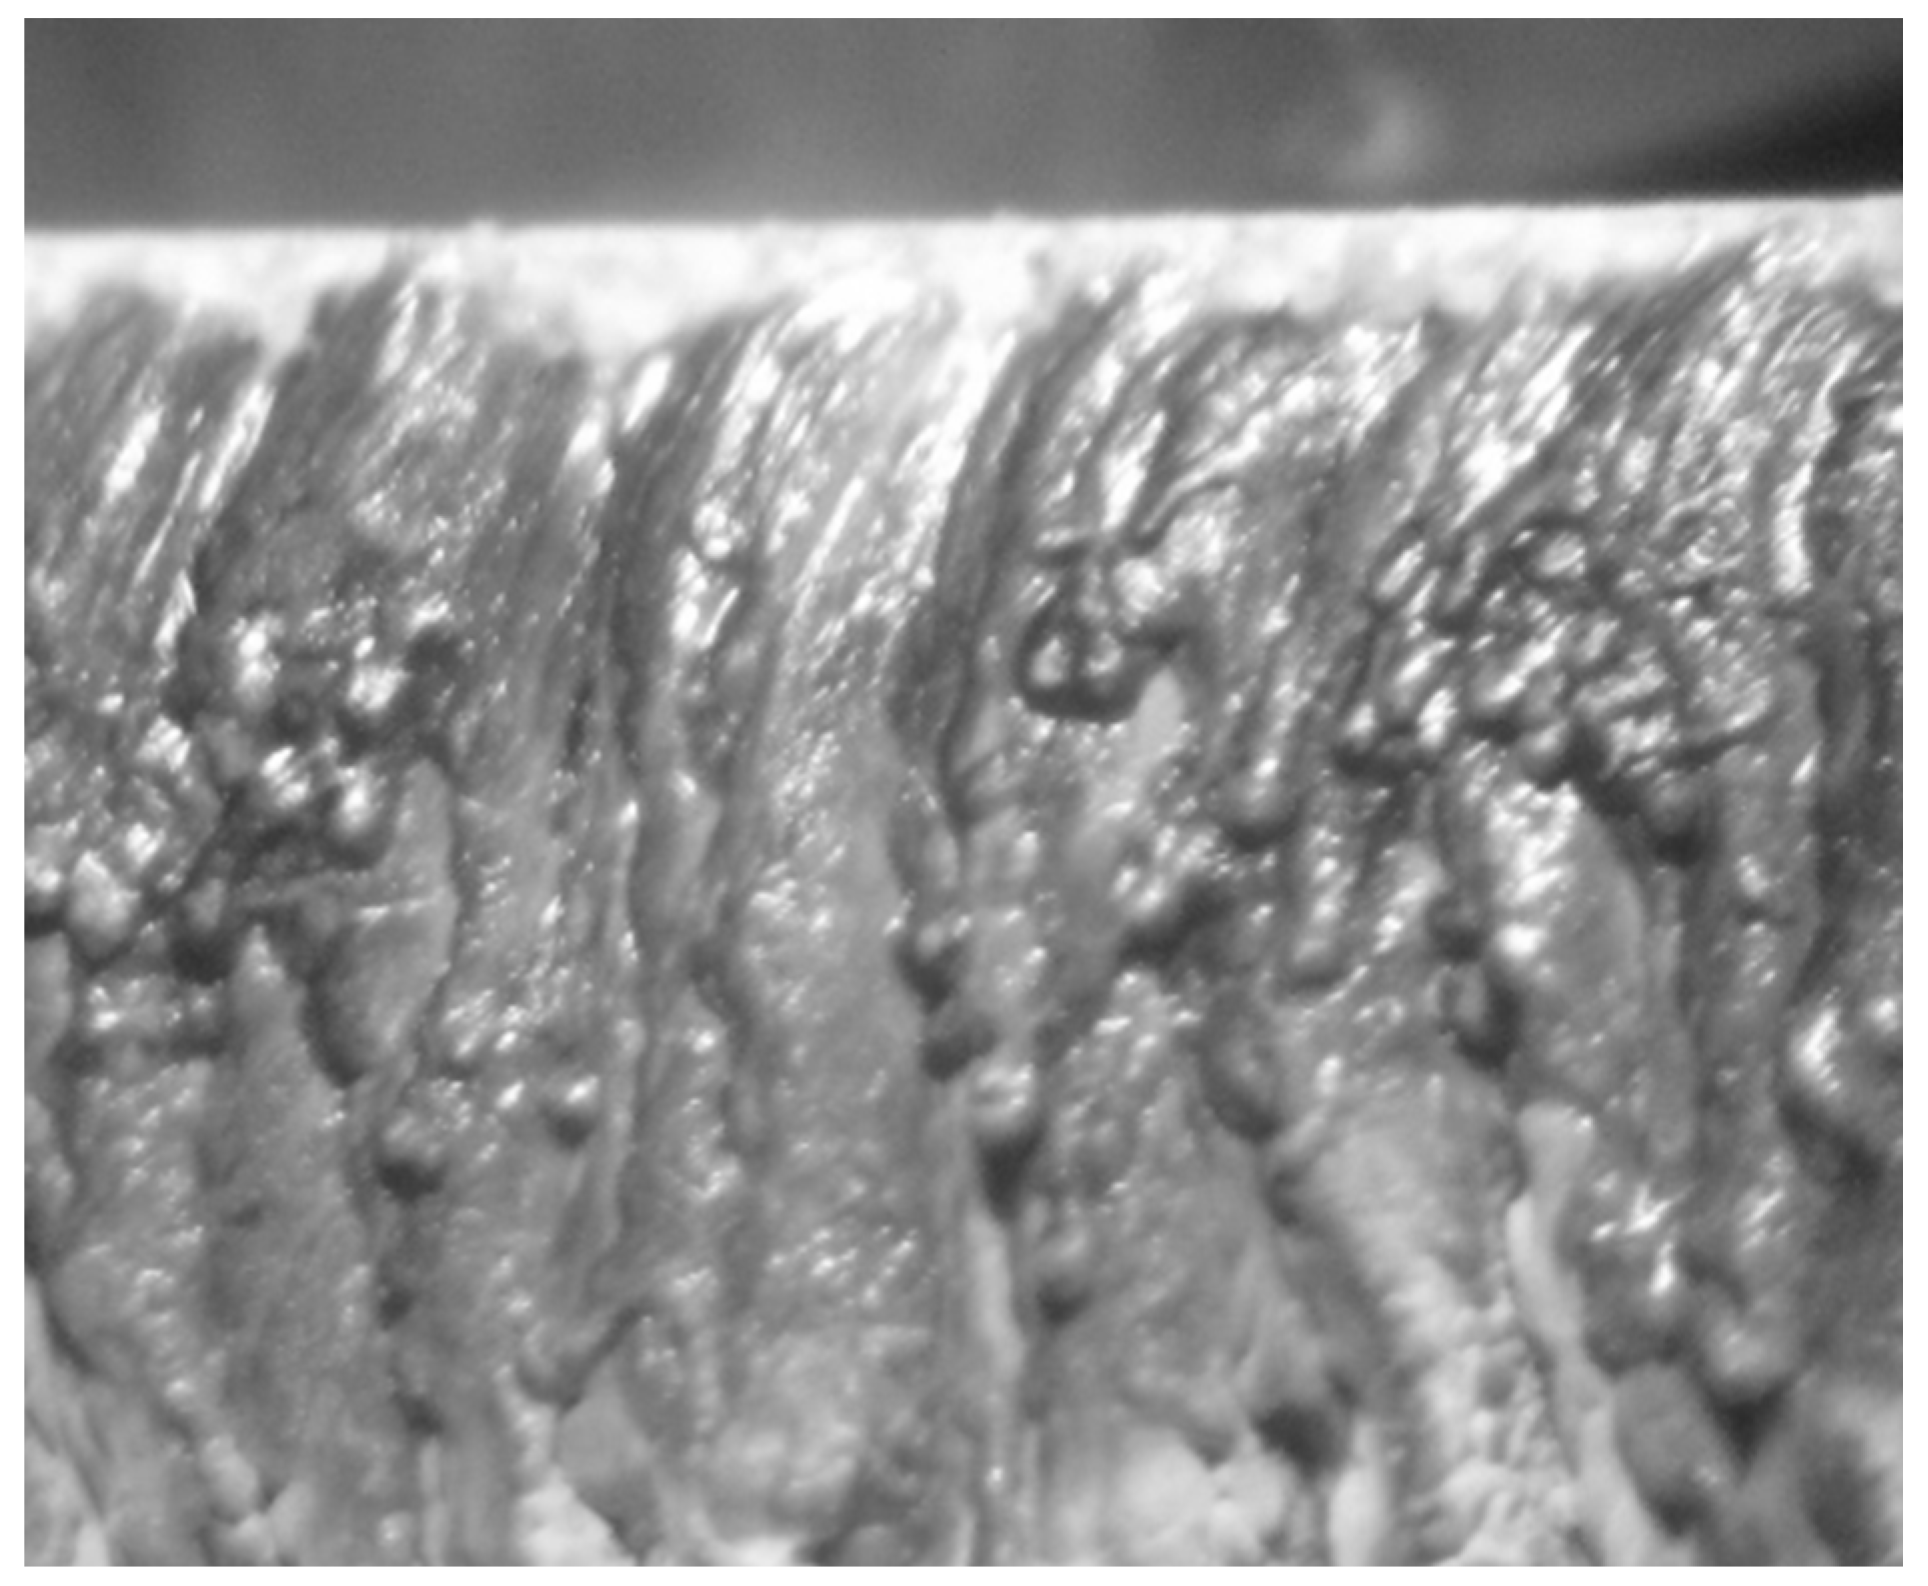

- Bucse, I.G.; Ristoscu, C.; Olei, B.A. Structural analysis of PM hydroxyapatite-based biocomposites elaborated by two-step sintering. JOAM 2015, 17, 1050–1054. [Google Scholar]

- Gingu, O.; Cojocaru, D.; Ristoscu, C.; Sima, G.; Teisanu, C.; Mangra, M. The influence of the foaming agent on the mechanical properties of the PM hydroxyapatite-based biocomposites processed by two-step sintering route. JOAM 2015, 17, 1044–1049. [Google Scholar]

- Benga, G.; Gingu, O.; Ciupitu, I.; Gruionu, L.; Pascu, I.; Moreno, J.C. Processing and Laser Micromachining of HAP Based Biocomposites. In Engineering the Future; Dudas, L., Ed.; IntechOpen: London, UK, 2010; pp. 1–26. [Google Scholar] [CrossRef]